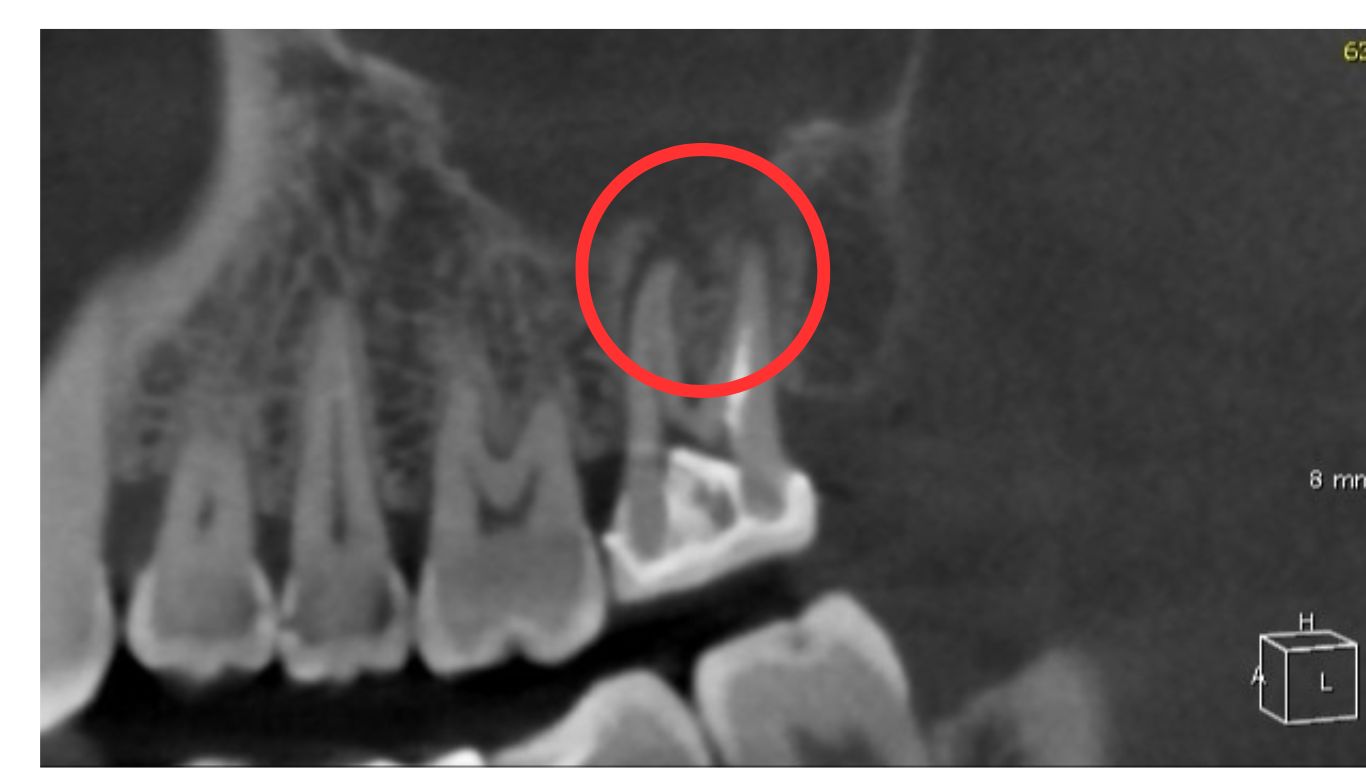

患部のCTを撮影したところ、根尖部(根の先端)に膿が貯まっていることを確認しました。

画像上では、根の先端にある黒く抜けている部分が根尖です。

この状態を根尖性歯周炎(Per)といいます。